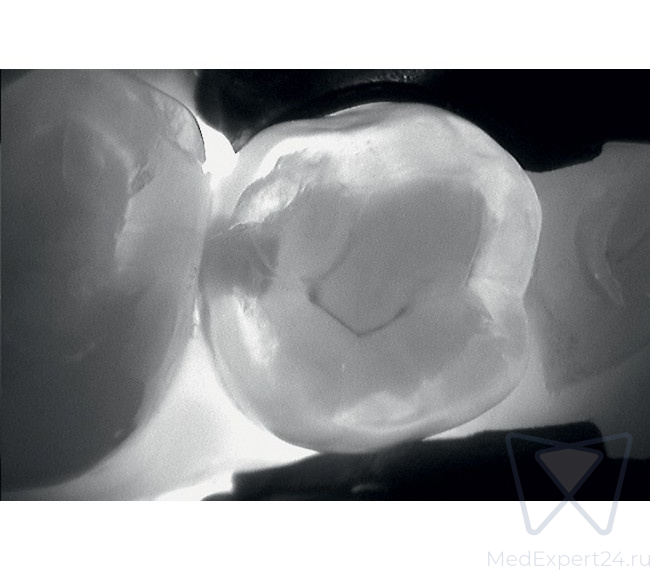

KaVo DIAGNOcam дает Вам полную уверенность в точности результата диагностики. С его помощью Вы сможете обнаружить кариозные поражения на самом раннем этапе развития.

KaVo DIAGNOcam позволяет визуализировать их на аппроксимальных и окклюзионных поверхностях зубов и обеспечивает проведение диагностики вторичного кариеса (при небольшом размере пломбы).